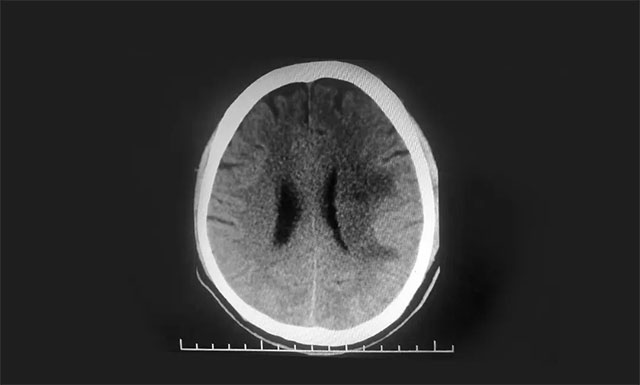

▲ 術(shù)后CT復(fù)查,出血基本已吸收

經(jīng)過一段時間住院和康復(fù)治療后,汪先生可以自行平穩(wěn)走動和爬樓梯,語言能力也恢復(fù)了正常。“我平時沒高血壓,熬夜那段時間卻頻頻頭痛,當(dāng)時太忙,疏忽了身體發(fā)出的危險信號,以后再也不敢這么拼命了。”汪先生感慨道。